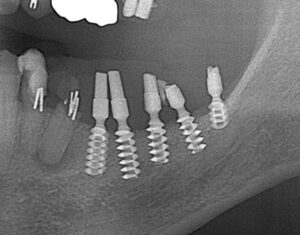

OGAインプラント

今ではほとんど見ないタイプのインプラントです。

私も当時このインプラントについて知識がなかったため、このインプラントを積極的に行われていた第一人者でもある先生にお話を伺いました。(現在は引退されていました)

このインプラントは1本1本が小さく、インプラントの一部が細くなっているため、細くなっている部位から破折している部位が数カ所ありました。

まだ使用できるインプラントは使用し、そうでないインプラントは撤去、スリーピングを行い対応しております。

このタイプのインプラントが、以前の治療で使用されていてお困りの方は、ご相談頂ければご対応が可能ですので、ご連絡頂ければと思います。